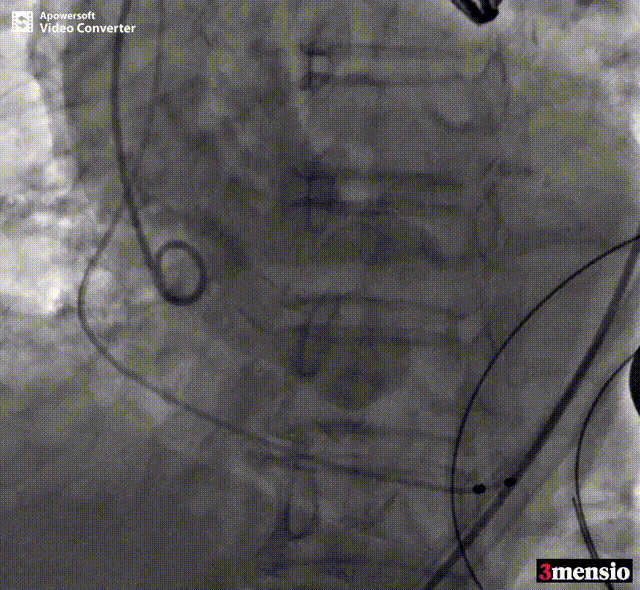

术中释放定位键后DSA影像图

术中瓣膜释放过程

患者全麻后,于左侧心尖3-4cm处进行微创手术切口。在DSA及超声引导下,输送Ken-Valve瓣膜系统进入左心室,边调弯边推送,使得瓣膜在术中始终保持较好的同轴性,从送入输送器到瓣膜释放不足十分钟。术后即刻患者返流消失,于外科杂交手术室拔除气管插管,次日即由ICU转入普通病房。

张海波教授:此病例为单纯的主动脉瓣关闭不全患者。CT分析提示,主动脉根部角度为78°,为重度“横位心”患者,给瓣膜的植入带来了巨大的挑战。术中采用了Ken-Valve输送系统,进入左心室后进行调弯,减少了对升主动脉的影响,从而增加了瓣环上的操作空间,了瓣膜的同轴性,整个手术过程十分顺畅。对于重度横位心、单纯主动脉瓣关闭不全的病例,这是难能可贵的。术后即刻患者返流消失,结果令人满意。由于Ken-Valve瓣膜具有独特的定位件及裙边设计,其他长支架自展瓣难以企及。